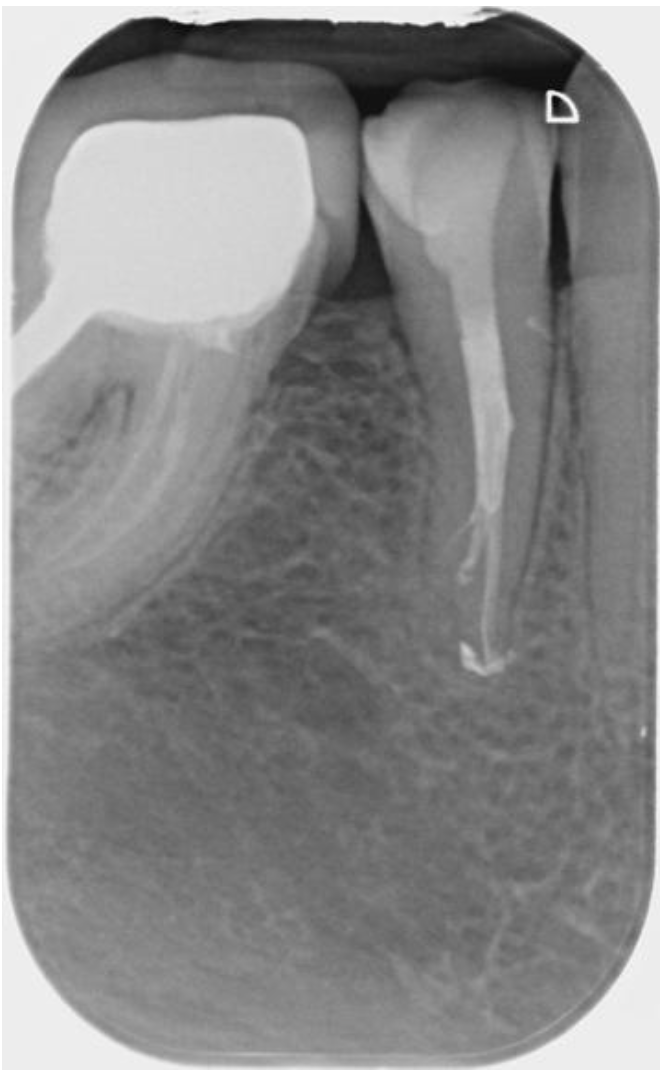

Below is the radiograph (displaying nice healing) taken at her 1-year review appointment, where the patient reported the tooth was symptom-free, which was pleasing: